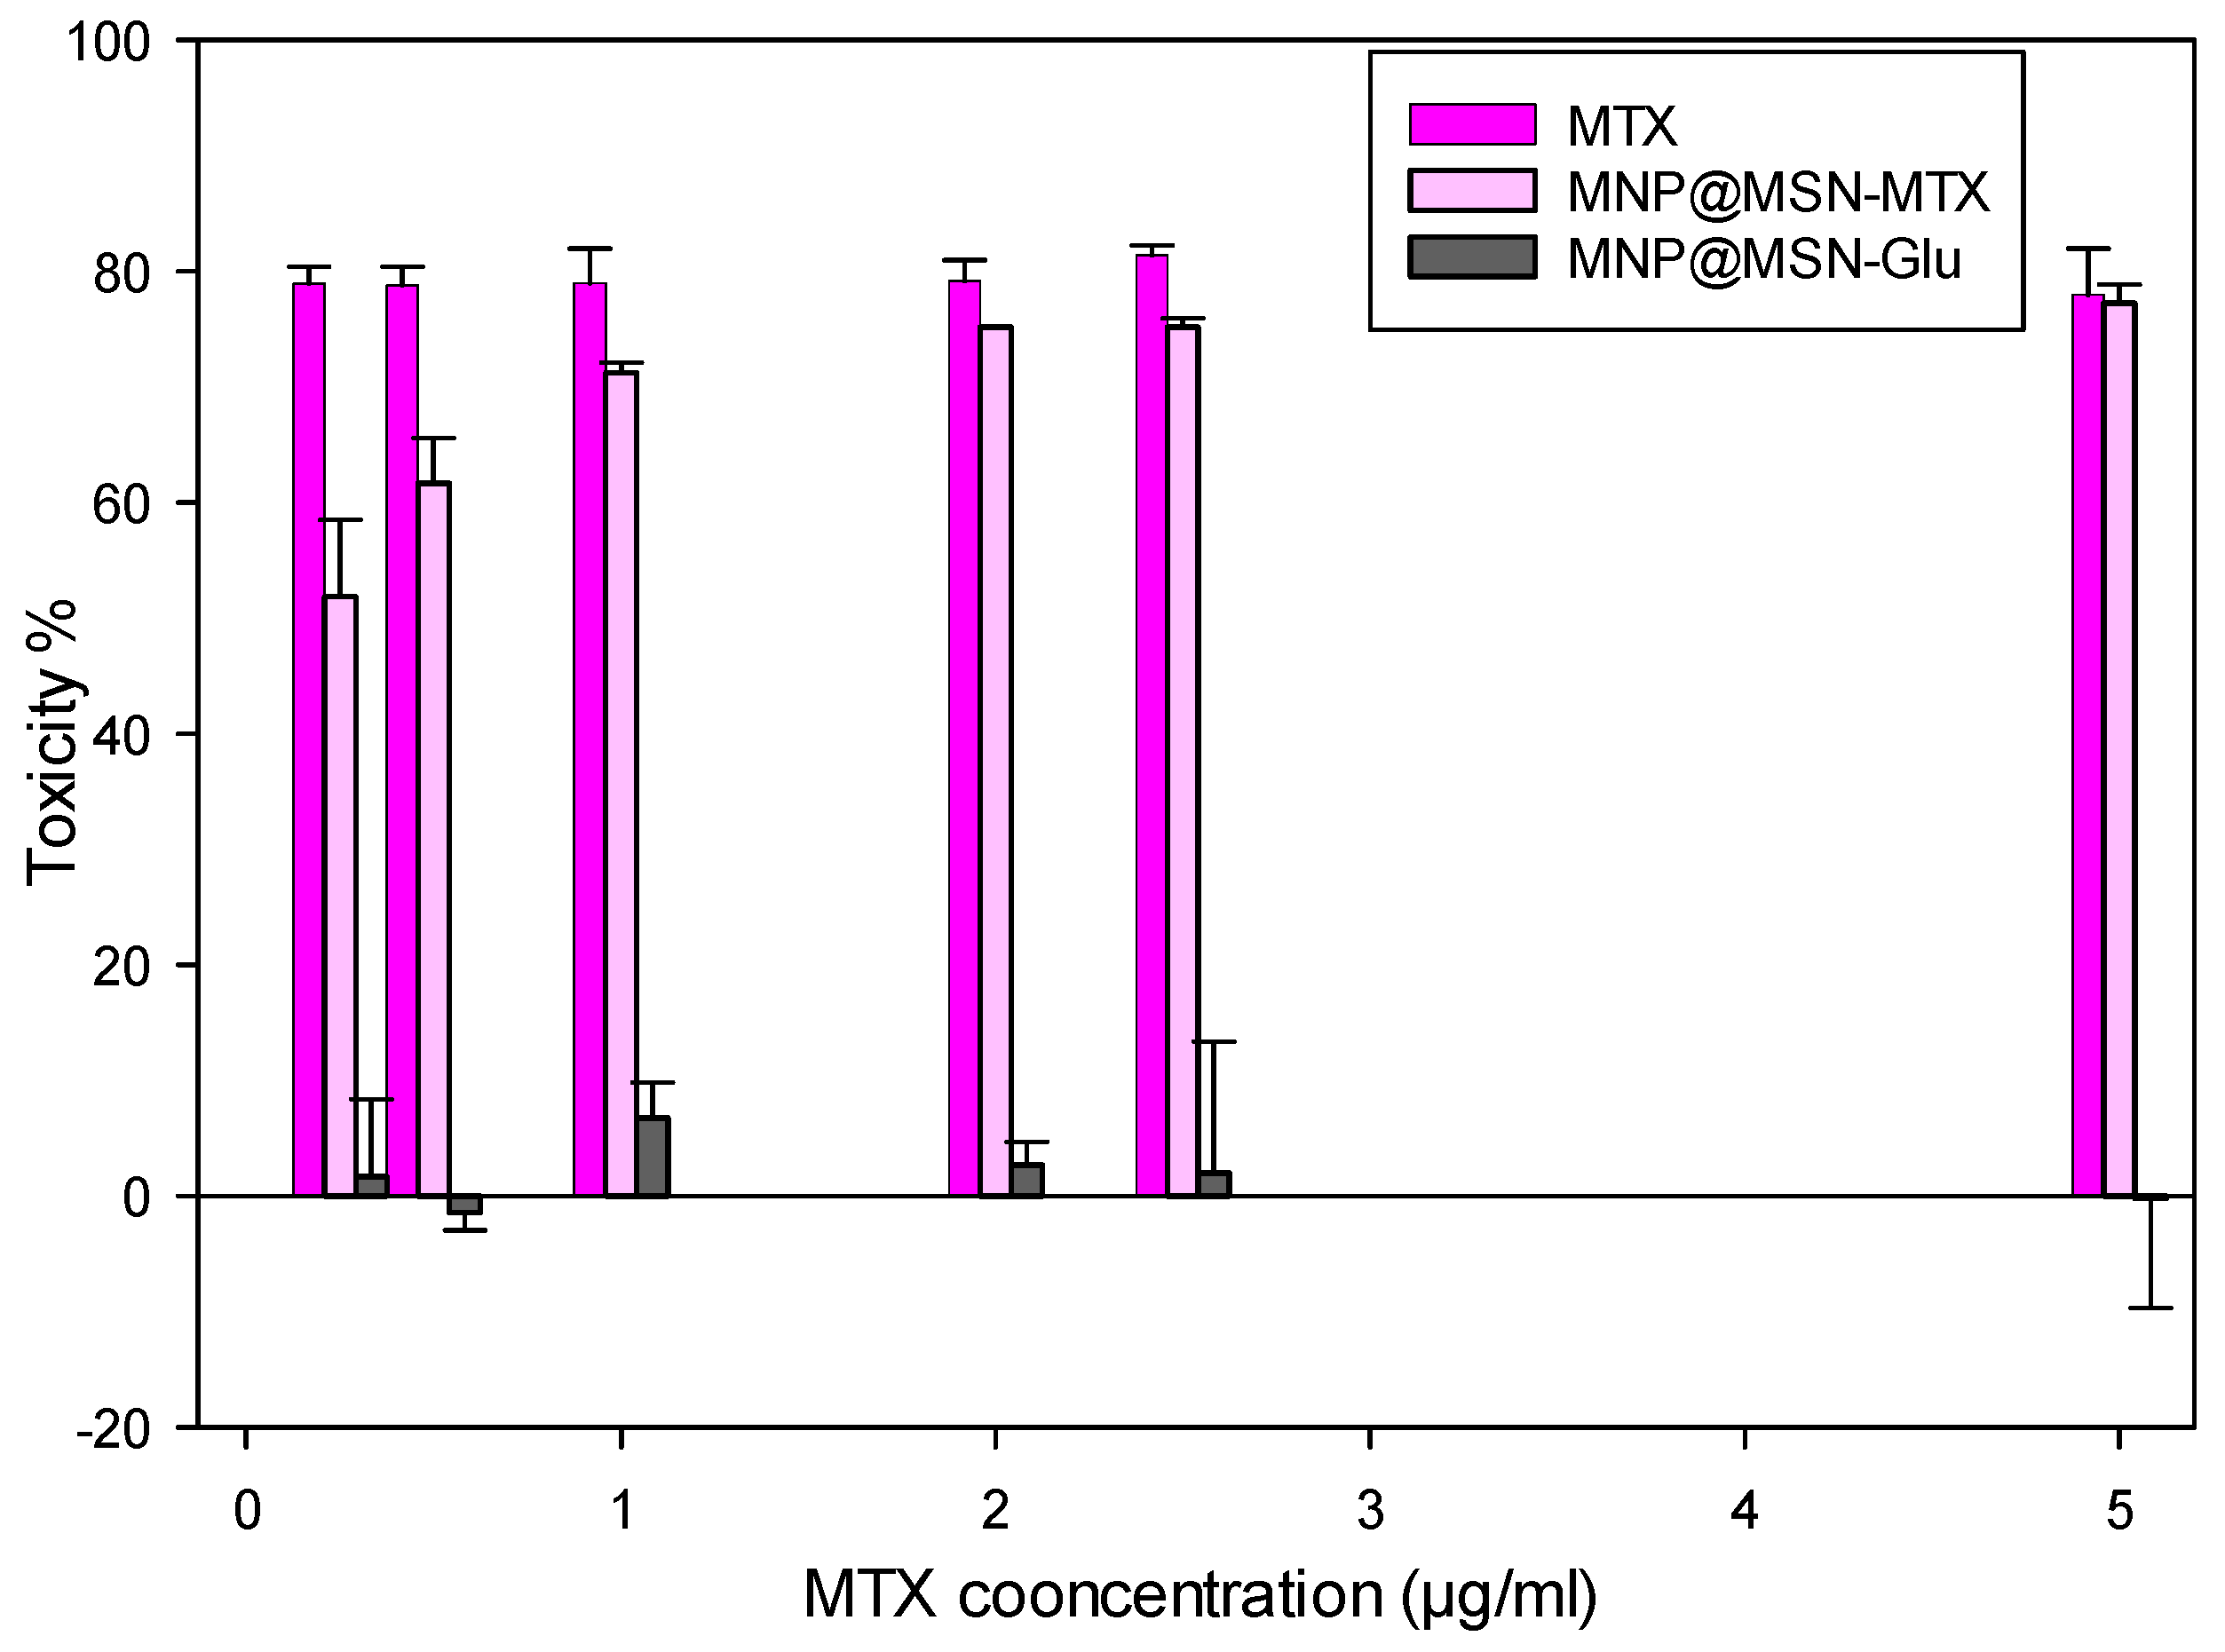

3.4. Cytotoxic Effect of MNP@MSN-Glu on 4T1 Cell Line